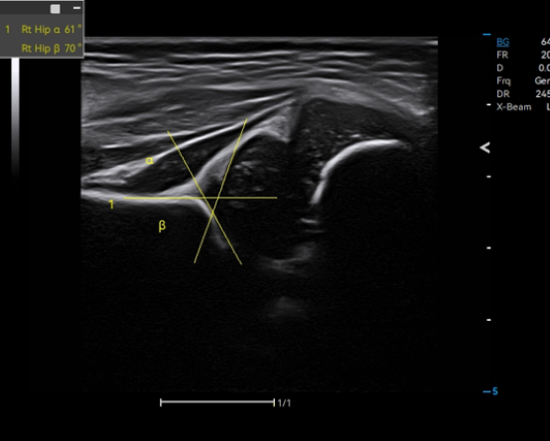

Auto Hip

Reliable evaluation of hip dysplasia by automatic identification of bone and cartilage baseline and top line, along with measurement of α and β angles.